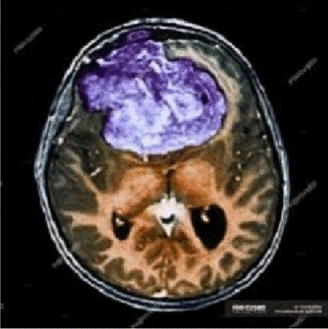

Image 2

View full size image